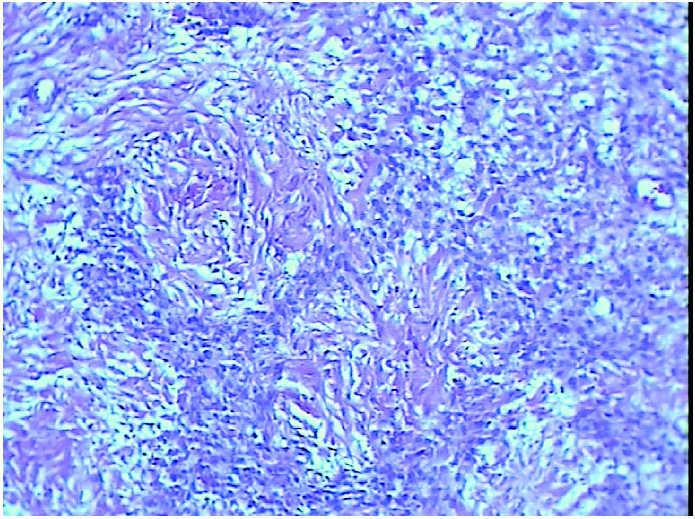

En el estudio microscópico se aprecia que las paredes de dicha formación quística están constituidas por células fusiformes y epitelioides, dispuestas con un patrón seudonodular, alternando con áreas edematosas y colagenizadas y con marcada vascularización (fig. 2). El estudio inmunohistoquímico pone de manifiesto la expresión de vimentina y actina específica de músculo liso, con ausencia de expresión de citoqueratinas de amplio espectro, proteína S-100 y CD34 (Master Diagnostic, Granada).

Figura 2.Imagen microscópica que muestra el patrón seudolobular, áreas hipercelulares junto a zonas colagenizadas (hematoxilina-eosina, ×40).